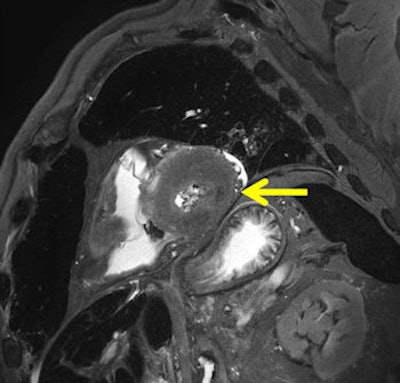

Chronic myocardial infarction in postmortem MRI (death occurred months to years after infarction). A T2-weighted short axis image depicts a severe shrinking of the lateral wall with broad decrease of signal (arrow). Autopsy demonstrated definite collagenous transformation of the infarcted inferior myocardium with scar-caused shrinking (not shown). Histology (H&E) showed cell-free collagen formation as the cause for the significant decrease of signal in MRI.